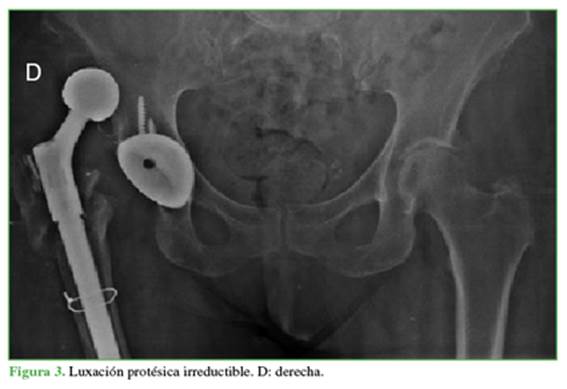

Luego de esta última cirugía, la paciente presenta episodios recurrentes de luxación protésica a partir del segundo mes del posoperatorio, en total 4 episodios, los 3 primeros tratados con reducción cerrada. En el cuarto episodio de luxación, no fue posible la reducción incruenta (Figura 3), y permaneció luxada hasta la realización de la revisión protésica a los 9 meses de la operación. Se contempló la preservación del cotilo no cementado osteointegrado y cementando en él mediante una copa de doble movilidad, con cambio, a su vez, del módulo proximal del componente femoral, que nos brinda la posibilidad del uso de un mayor offset –ventaja vinculada con la modularidad del vástago–, preservando la tensión, la longitud y la reductibilidad de la prótesis.